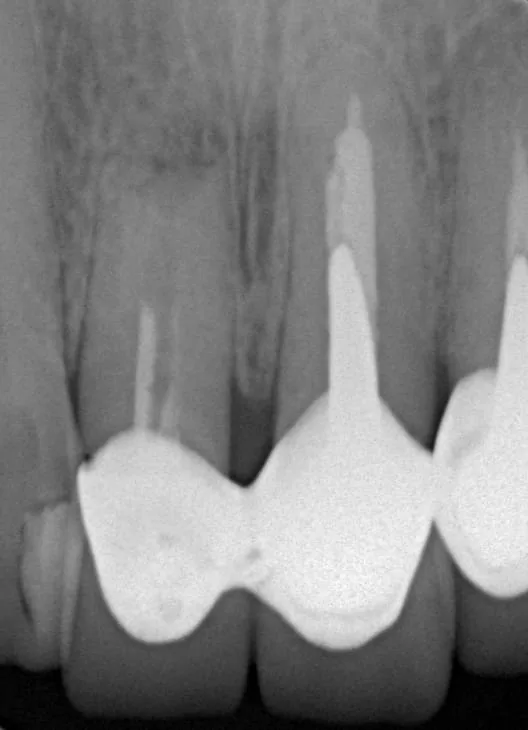

此患者多年前右上大門牙接受根尖切除術,但並未做根管治療及根尖逆填充,導致根尖吸收、搖動度過大以及咬合不良(圖1)。

(圖1: 治療前X光片可見牙根已被吸收)